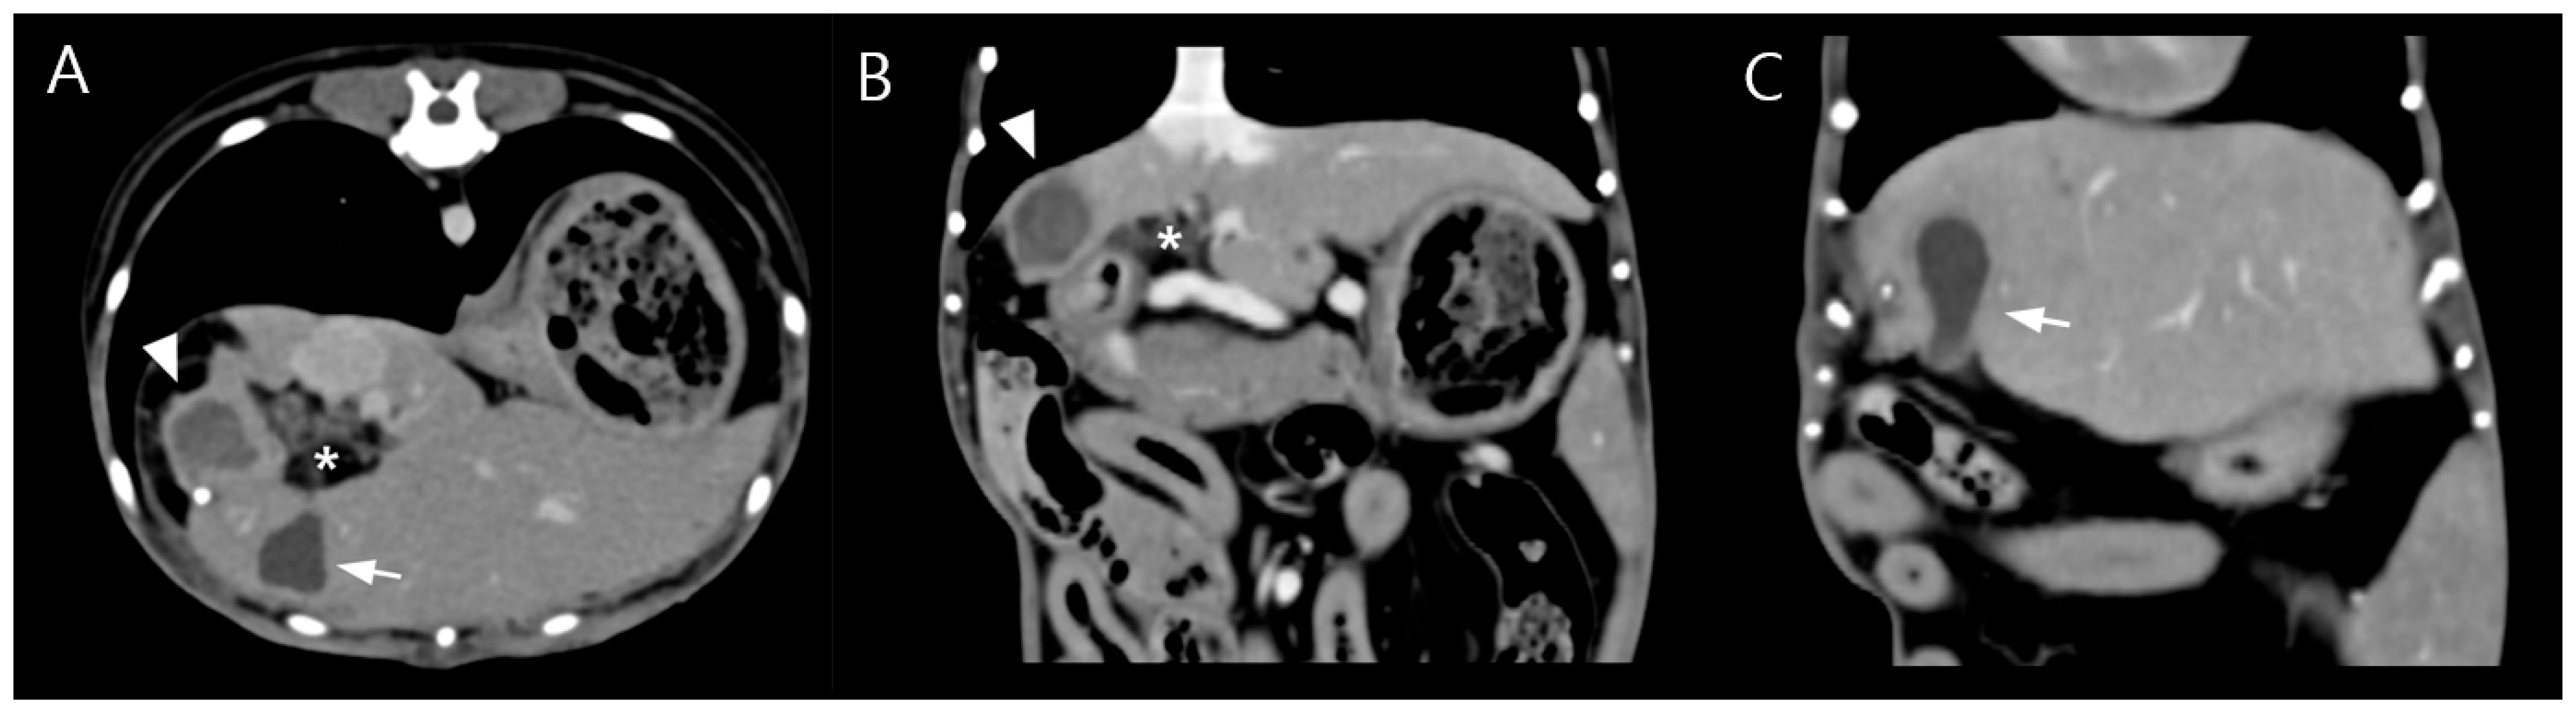

Due to poor response to medical management and the potential for disease progression, surgical intervention was elected on day 5 of hospitalization with owner consent. Preoperative CT imaging revealed a hepatic abscess measuring 1.53 × 1.43 × 1.71 cm, located on the caudomedial surface of the right medial hepatic lobe near the junction of the gallbladder and the cystic duct (Figure 3). On contrast-enhanced CT examination, the hepatic abscess and gallbladder were simultaneously visualized on transverse images. On dorsal plane CT reconstructions, the hepatic abscess was most clearly identified on one slice, while the gallbladder was visualized approximately two slices ventral to this level. Although these structures were not visible within the same dorsal plane slice, their close anatomical proximity was evident.

Figure 3.

Preoperative contrast-enhanced computed tomography (CT) images (soft tissue window; WL 100, WW 395). (A) Transverse image showing a well-defined hypoattenuating lesion adjacent to the gallbladder (arrow) with peripheral rim enhancement (arrowhead), consistent with a hepatic abscess, and surrounding fat stranding (asterisk), suggestive of localized inflammation. (B) Dorsal plane reconstruction demonstrating the hepatic abscess at its maximal extent with peripheral rim enhancement (arrowhead). Surrounding fat stranding adjacent to the lesion (asterisk), corresponding to the same region identified in subfigure A, indicates inflammatory changes in the adjacent adipose tissue. (C) A more ventral dorsal slice illustrating the gallbladder (arrow), highlighting the close anatomic proximity between the hepatic abscess and the gallbladder–cystic duct junction. Although the hepatic abscess and gallbladder are not visualized within the same dorsal plane slice, their close anatomic relationship is evident across adjacent sections.